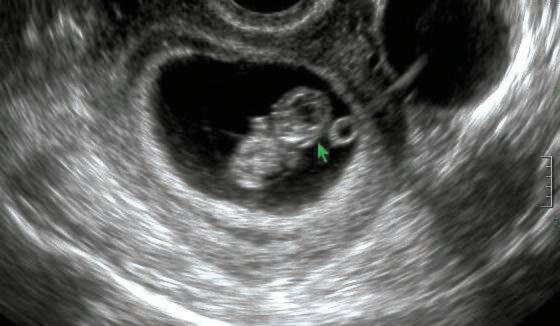

30년 전만 해도 상상하기 힘든 모습이다. 국내 출생아 성비 불균형이 가장 극심했던 해인 1990년, 여아 100명이 태어날 때 남아 116명이 태어났다. 당시 첫째아 성비는 108명이지만, 둘째아는 117.1명으로 뛰어오르고, 셋째아 이상에서는 193.7명이라는 기형적인 성비가 나타났다. 당시 성비 불균형은 경북(130.7명), 대구(129.7명), 경남(124.7명) 등 영남지역에서 더 심하게 나타났는데, 대구의 셋째아 이상 성비는 392.2에 달했다. 전문가들은 “아들 하나는 낳아야 한다”는 남아 선호 사상이 강했고, 초음파 기기가 도입되면서 태아 성 감별과 선별 낙태가 성행한 영향이라고 설명한다. 이런 추세는 1980년대 후반~1990년 초반 계속 이어졌는데, 1990년의 경우 ‘백말띠 해에 태어난 여자는 팔자가 사납다’는 속설에 여아 출산을 더 기피했다고 알려졌다.

최안나 산부인과 전문의는 “1980년대 이전에는 아들을 낳고 싶다면 낳을 때까지 임신ㆍ출산했지만, 산아제한 정책이 본격화하면서 하나 또는 둘만 낳아 잘 기르자는 분위기가 퍼졌다”라고 말했다. 그는 “이후 산전검사와 초음파 기기가 도입됐고, 하나 아니면 둘을 낳다 보니 ‘내가 원하는 아이’를 낳겠다는 생각이 더해지면서 원하지 않는 아이들에 대한 낙태가 흔했다”라고 설명했다.